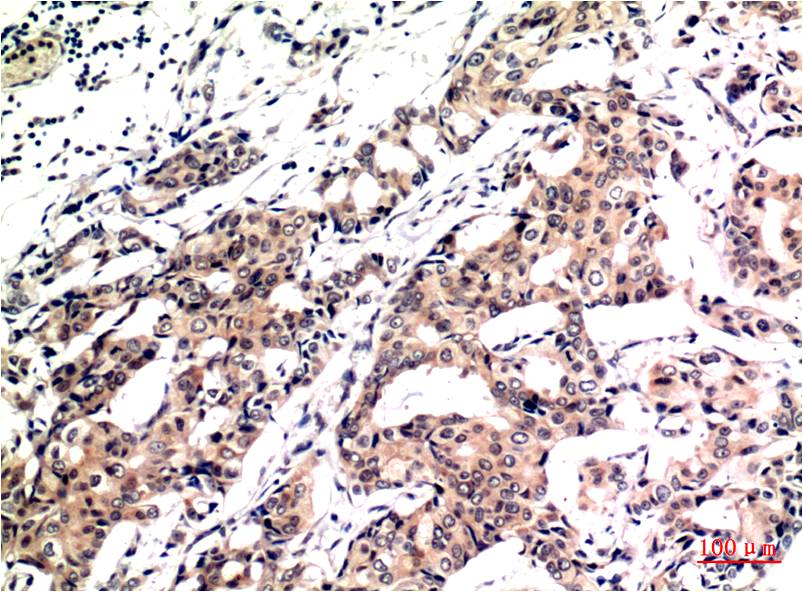

• Immunohistochemistry analysis of paraffin-embedded Human Breast Carcinoma Tissue using Ubiquitin antibody.High-pressure and temperature Sodium Citrate pH 6.0 was used for antigen retrieval.